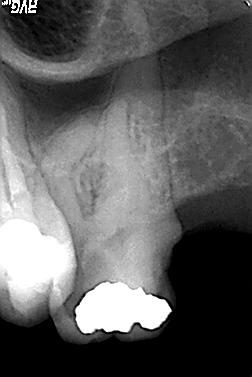

Röntgenologischer Ausgangsbefund im Febr. 2003 mit caries profunda, starken Krümmungen sowohl der mesiobuccalen wie auch der distobuccalen Wurzeln

Zustand unmittelbar vor Behandlungsbeginn im Juni 2003. Die Fraktur des distalen Zahnanteils hat die Patientin jetzt zur Einwilligung in die Behandlung motiviert. Auffällig ist in dieser Projektion die besonders starke Krümmung der mb Wurzel sowie die knochennahe Defektlage distal. Es erfolgte zunächst die Kariesentfernung gefolgt von einer chirurgischen Kronenverlängerung zur Herstellung der biologischen Breite sowie Ermöglichung des sog. Ferrule-Effektes. Danach wurde der Zahn adhäsiv aufgebaut. Erst jetzt wurde mit der eigentlichen WKB begonnen